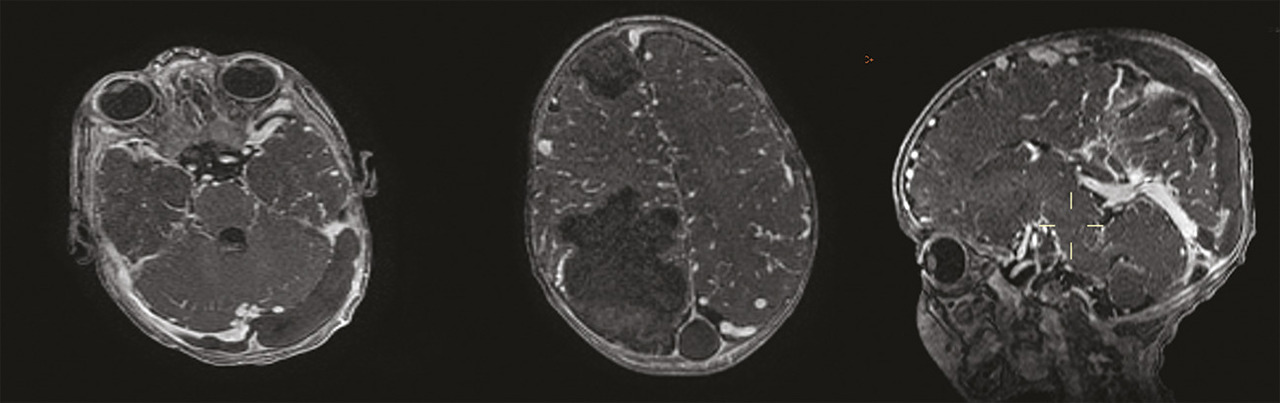

Ce nourrisson de 5 mois était admis aux urgences pour une crise convulsive généralisée. Issu d’un mariage consanguin, il était né par voie basse, sans notion de souffrance néonatale ni antécédents pathologiques notables. L’examen clinique trouvait un syndrome méningé fébrile. Un bilan biologique, une ponction lombaire, une tomodensitométrie et une imagerie par résonance magnétique cérébrales (fig. 1 et 2) étaient réalisés en urgence. Les prélèvements sanguins et du liquide céphalorachidien avaient un aspect lactescent, en faveur d’une méningite bactérienne, et le bilan lipidique était très perturbé : hypercholestérolémie totale à 17 g/L avec un LDL-cholestérol très élevé et un HDL-cholestérol très bas. L’imagerie montrait des plages lésionnelles parenchymateuses cérébrales droites, frontale et pariétale, de signal graisseux et une thrombophlébite cérébrale des sinus longitudinal et latéraux ainsi que quelques veines corticales de signal graisseux. Le diagnostic d’hypercholestérolémie primaire était posé. Le nourrisson était hospitalisé en réanimation et mis sous régime hypolipidémiant.